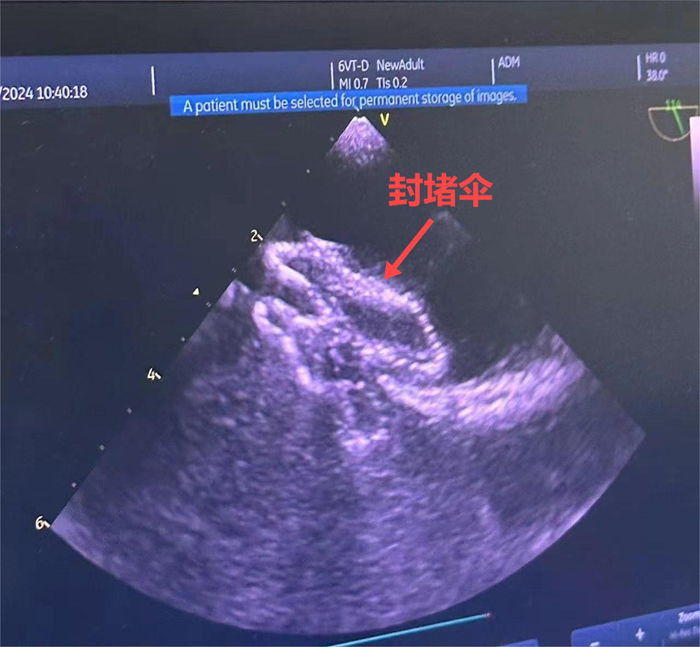

患者郝女士在潞河医院进行大隐静脉曲张射频手术期间,检查心脏彩超时发现房间隔缺损(II孔型)。郝女士从血管外科出院后为求治疗房间隔缺损住进了心脏外科。本着对患者负责的态度,完善术前检查后全科进行了病例讨论,制定了局麻超声引导下房间隔缺损封堵手术方案。手术在手术室进行,由杨海平主任团队独立完成,经术中食道超声引导、评估,房缺封堵效果满意,无过隔血流。术后六小时郝女士即可以下床活动,术后第二天恢复良好,顺利出院。

潞河医院心脏外科可以为房间隔缺损患者施行开胸手术、小切口矫治、胸腔镜手术以及介入封堵术等治疗方式。术中食道超声引导下房间隔缺损封堵术有无射线辐射、耐受性好、痛苦小、费用低、术后恢复快等优势。潞河医院心脏外科将会继续努力,进一步提高先心病的治疗水平,为先心病患者提供更多的新的治疗选择。